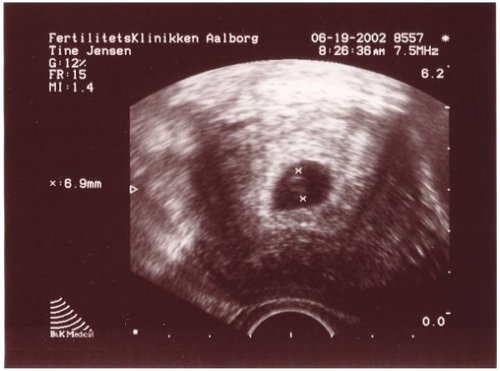

1.

6 uger